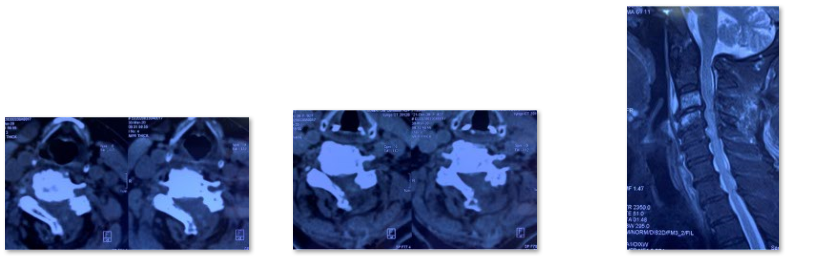

颈椎管狭窄症也是中老年人常见脊柱疾病,在椎管狭窄症发病率中仅次于腰椎管狭窄症。颈椎管狭窄症:构成颈椎管各解剖结构因发育性或退变因素造成骨性或纤维性退变引起一个或多个节段官腔狭窄导致脊髓血液循环障、脊髓及神经根压迫症者为颈椎管狭窄症。主要症状为1.感觉障碍:四肢麻木、过敏或疼痛,胸腹骨盆区发紧(束带感),严重者可有呼吸困难;2.运动障碍:四肢无力、僵硬不灵活,多数有下肢无力沉重、脚落地似踩棉花感,站立不稳,加重可出现四肢瘫痪;3.大小便障碍。颈椎管狭窄症患者CT或MRI通常表现为多节段颈椎间盘突出、黄韧带增生肥厚,颈椎椎管容积大大减小,脊髓多节段受压。

术前

术中透视

术后